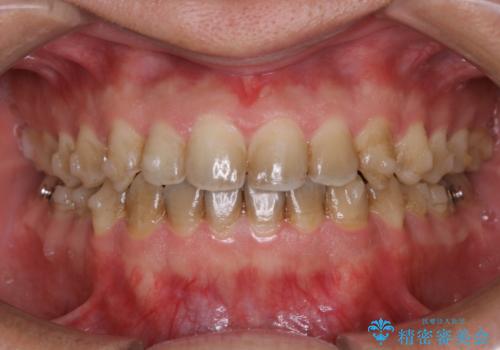

- もともとホワイトスポット(エナメル質形成不全)が全体的に目立つ歯だったので処置後ホワイトスポットがより白くなりました。

レーザーホワイトニング3回照射しました。

ホワイトスポットは一時的に白く目立ちますが、馴染んでいきます。